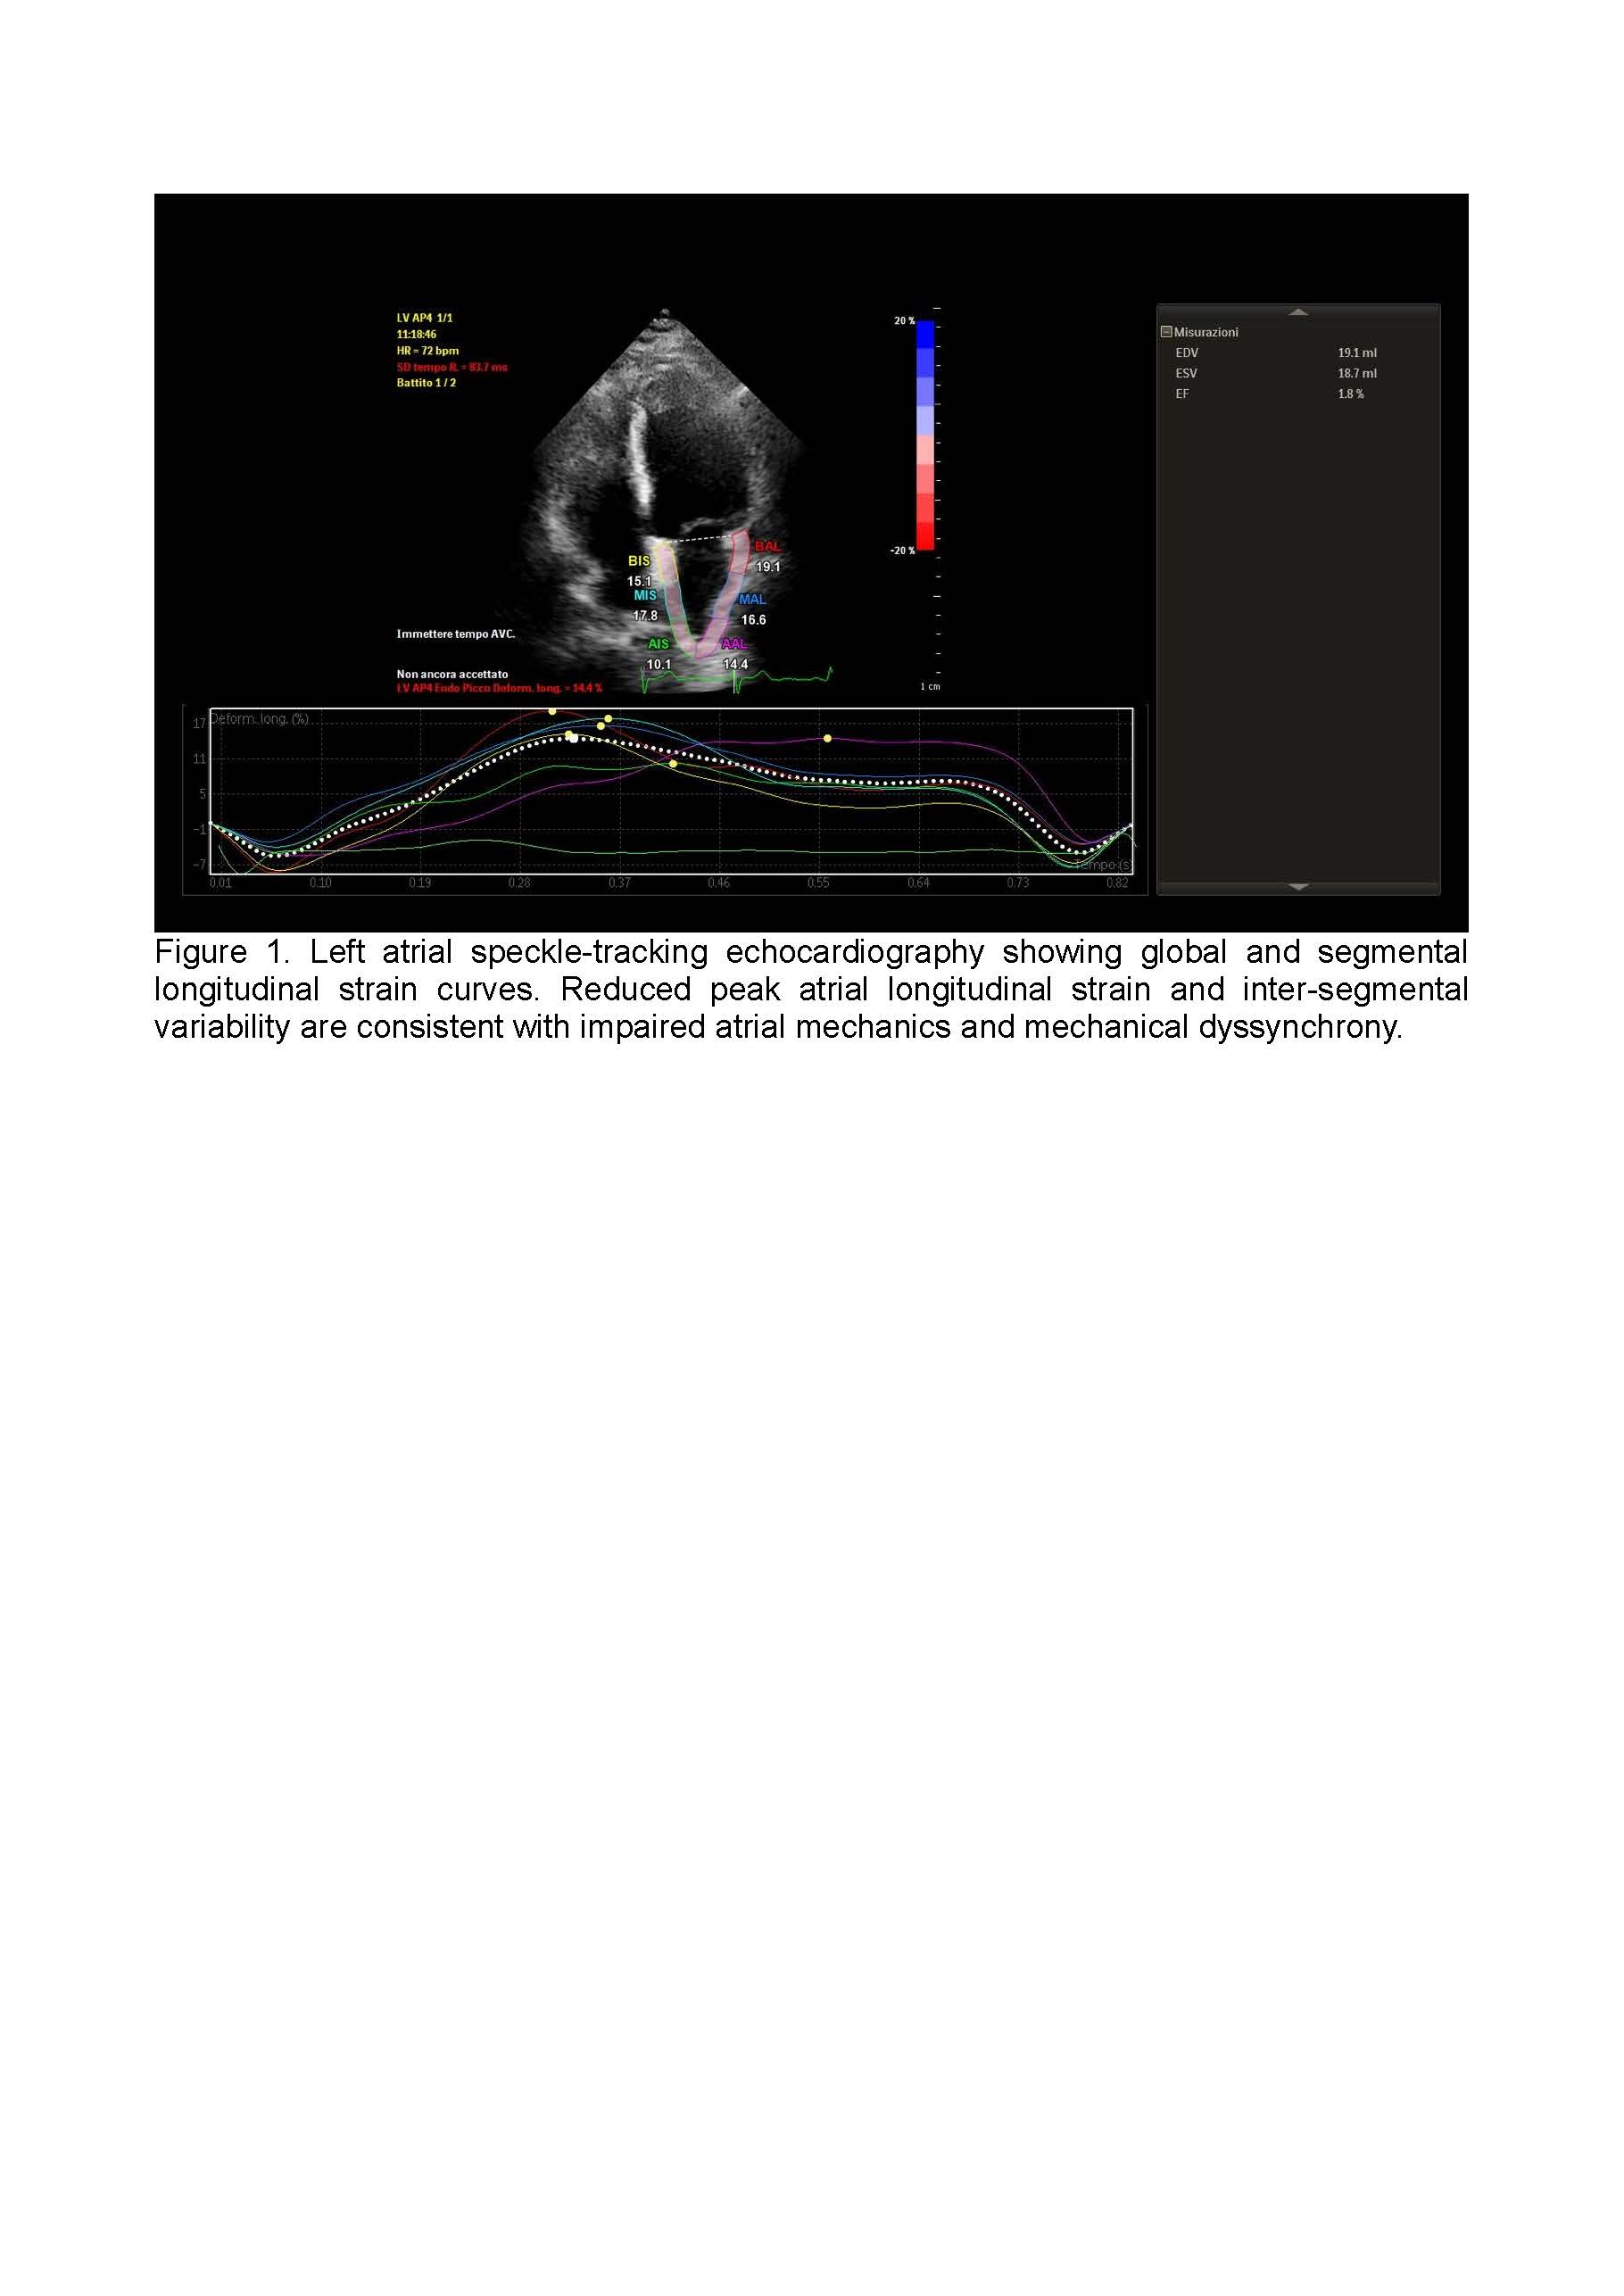

Background: Atrial fibrillation (AF) is a multifactorial arrhythmia in which epicardial adipose tissue (EAT) has emerged as a key contributor to atrial structural, electrical, and functional remodeling. Left atrial epicardial adipose tissue (LA-EAT), through endocrine, paracrine, and mechanical mechanisms, promotes inflammation, fibrosis, and atrial dyssynchrony. Early identification of atrial dysfunction is essential to improve risk stratification and guide therapeutic strategies. Methods: We performed a narrative review focusing on the pathophysiological relationship between left atrial epicardial adipose tissue and atrial remodeling in patients with atrial fibrillation. Particular attention was given to non-invasive imaging techniques, with emphasis on speckle-tracking echocardiography for the assessment of left atrial strain. Strain parameters, including reservoir, conduit, and contractile function, were analyzed in relation to epicardial adipose tissue burden and markers of atrial remodeling. In addition, emerging therapeutic strategies targeting epicardial adipose tissue were reviewed for their potential impact on atrial function and arrhythmia outcomes. Results: Reduced left atrial strain parameters are consistently associated with increased LA-EAT and advanced atrial remodeling in patients with atrial fibrillation. Strain imaging allows early detection of atrial dysfunction before overt structural changes occur and improves identification of patients at higher risk of AF recurrence. The integration of strain analysis with volumetric atrial assessment enhances diagnostic accuracy and patient stratification. Therapeutic interventions such as weight reduction and GLP-1 receptor agonists show promising effects in reducing EAT volume and mitigating atrial remodeling, potentially improving ablation outcomes. Conclusions: Left atrial strain imaging represents a valuable non-invasive tool for assessing EAT-related atrial remodeling in patients with atrial fibrillation. Its integration into routine clinical practice may optimize patient selection, guide therapeutic decisions, and improve long-term outcomes in AF management.